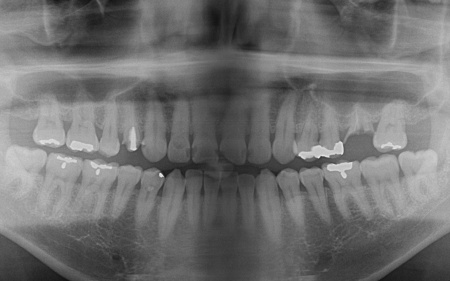

40代男性 長年放置していた虫歯や根尖性歯周炎などの口腔トラブルを全体的に治療した症例

「虫歯を長年放置してしまったので治療をしたい。また、見た目や噛み合わせの改善などを含めた、全体的な治療も行いたい」とご相談いただきました。

患者様は、10年ぶりに歯科医院を受診したとのことです。

レントゲン撮影をして詳しく検査したところ、複数の小さな虫歯が見られました。

また右上奥歯には、歯根の先に炎症が起きて膿が溜まる根尖性(こんせんせい)歯周炎が認められます。

さらに、左上奥歯(第1大臼歯)は温存が難しい状態でした。